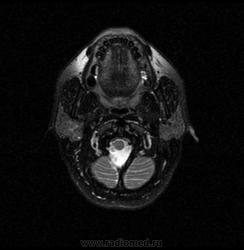

06.06.2011 МРТ - головы и шеи.

Пацентка 36 лет, с жалобами на припухлось в околоушной области справа.

В глубокой доле  правой околоушной железы  на фоне неизмененной паренхимы зона  гетерогенного по Т2, гипоинтенсивного по Т1  с единичными гиперинтенсивными включениями.При контрастировании- накопление контраста диффузное неоднородное и по периферии.Рискну предположить злокачественное образование ( аденокарцинома) с низкой степенью злокачественности( есть капсула, экспансивный рост).Сильно не расстреливайте.

Проблема в том, что перед челюстно-лицевым хирургом стоит распространенность любого объемного процесса, в данном случае все упирается в возмможную травму лицевого нерва и конечно же с дальнейшим его парезом, а ведь женщина  еще молодая. Образование имеет тонкостенную оболочку, по структуре неоднородно, с наличием кальцината, при этом МР-сигнал от окружающих анатомических структур(как костных так и мышечных) не изменен, т.е. об инфильтративном росте речи не идет, в какой то степени доброкачественное. В конкретном случае лицевой нерв с ретромандибулярной веной просто несколько оттеснен.

По гистологии аденома околоушной слюнной железы, но после удаления пока сохраняется парез лицевой мускулатуры, возможно временный.